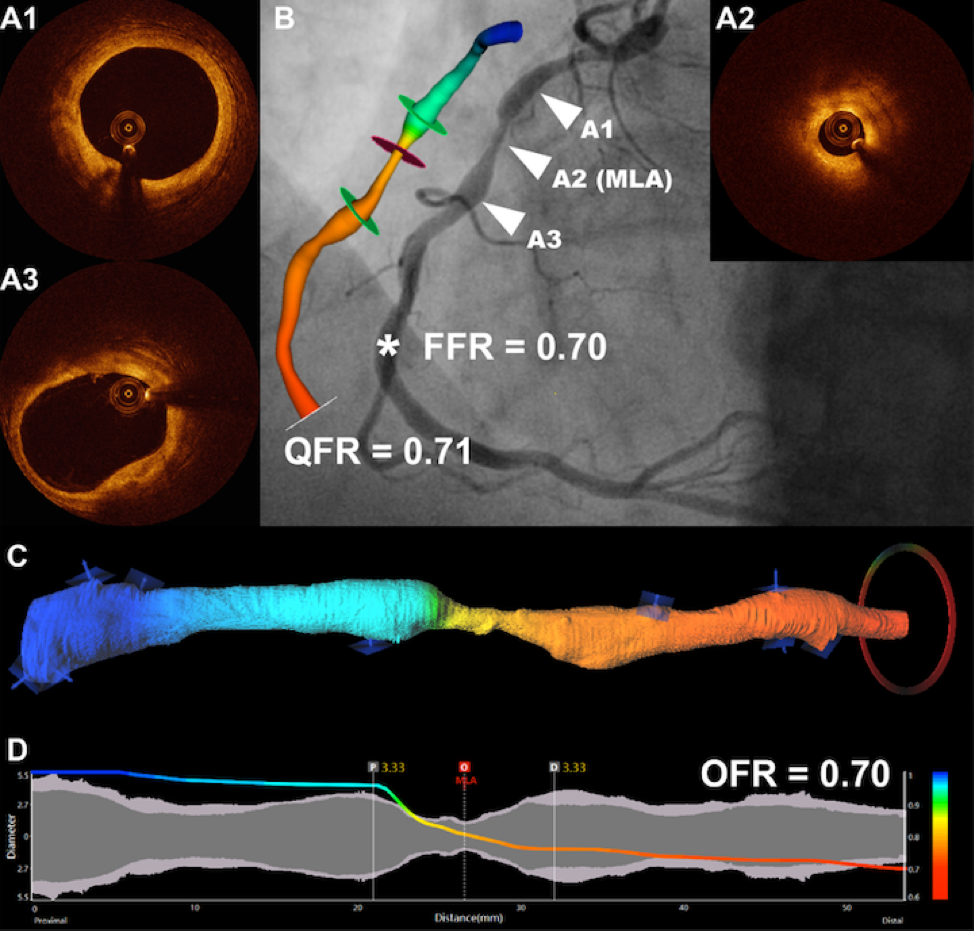

图1:基于冠脉造影的QFR与基于腔内影像OCT的OFR(图片来自于综述文章)